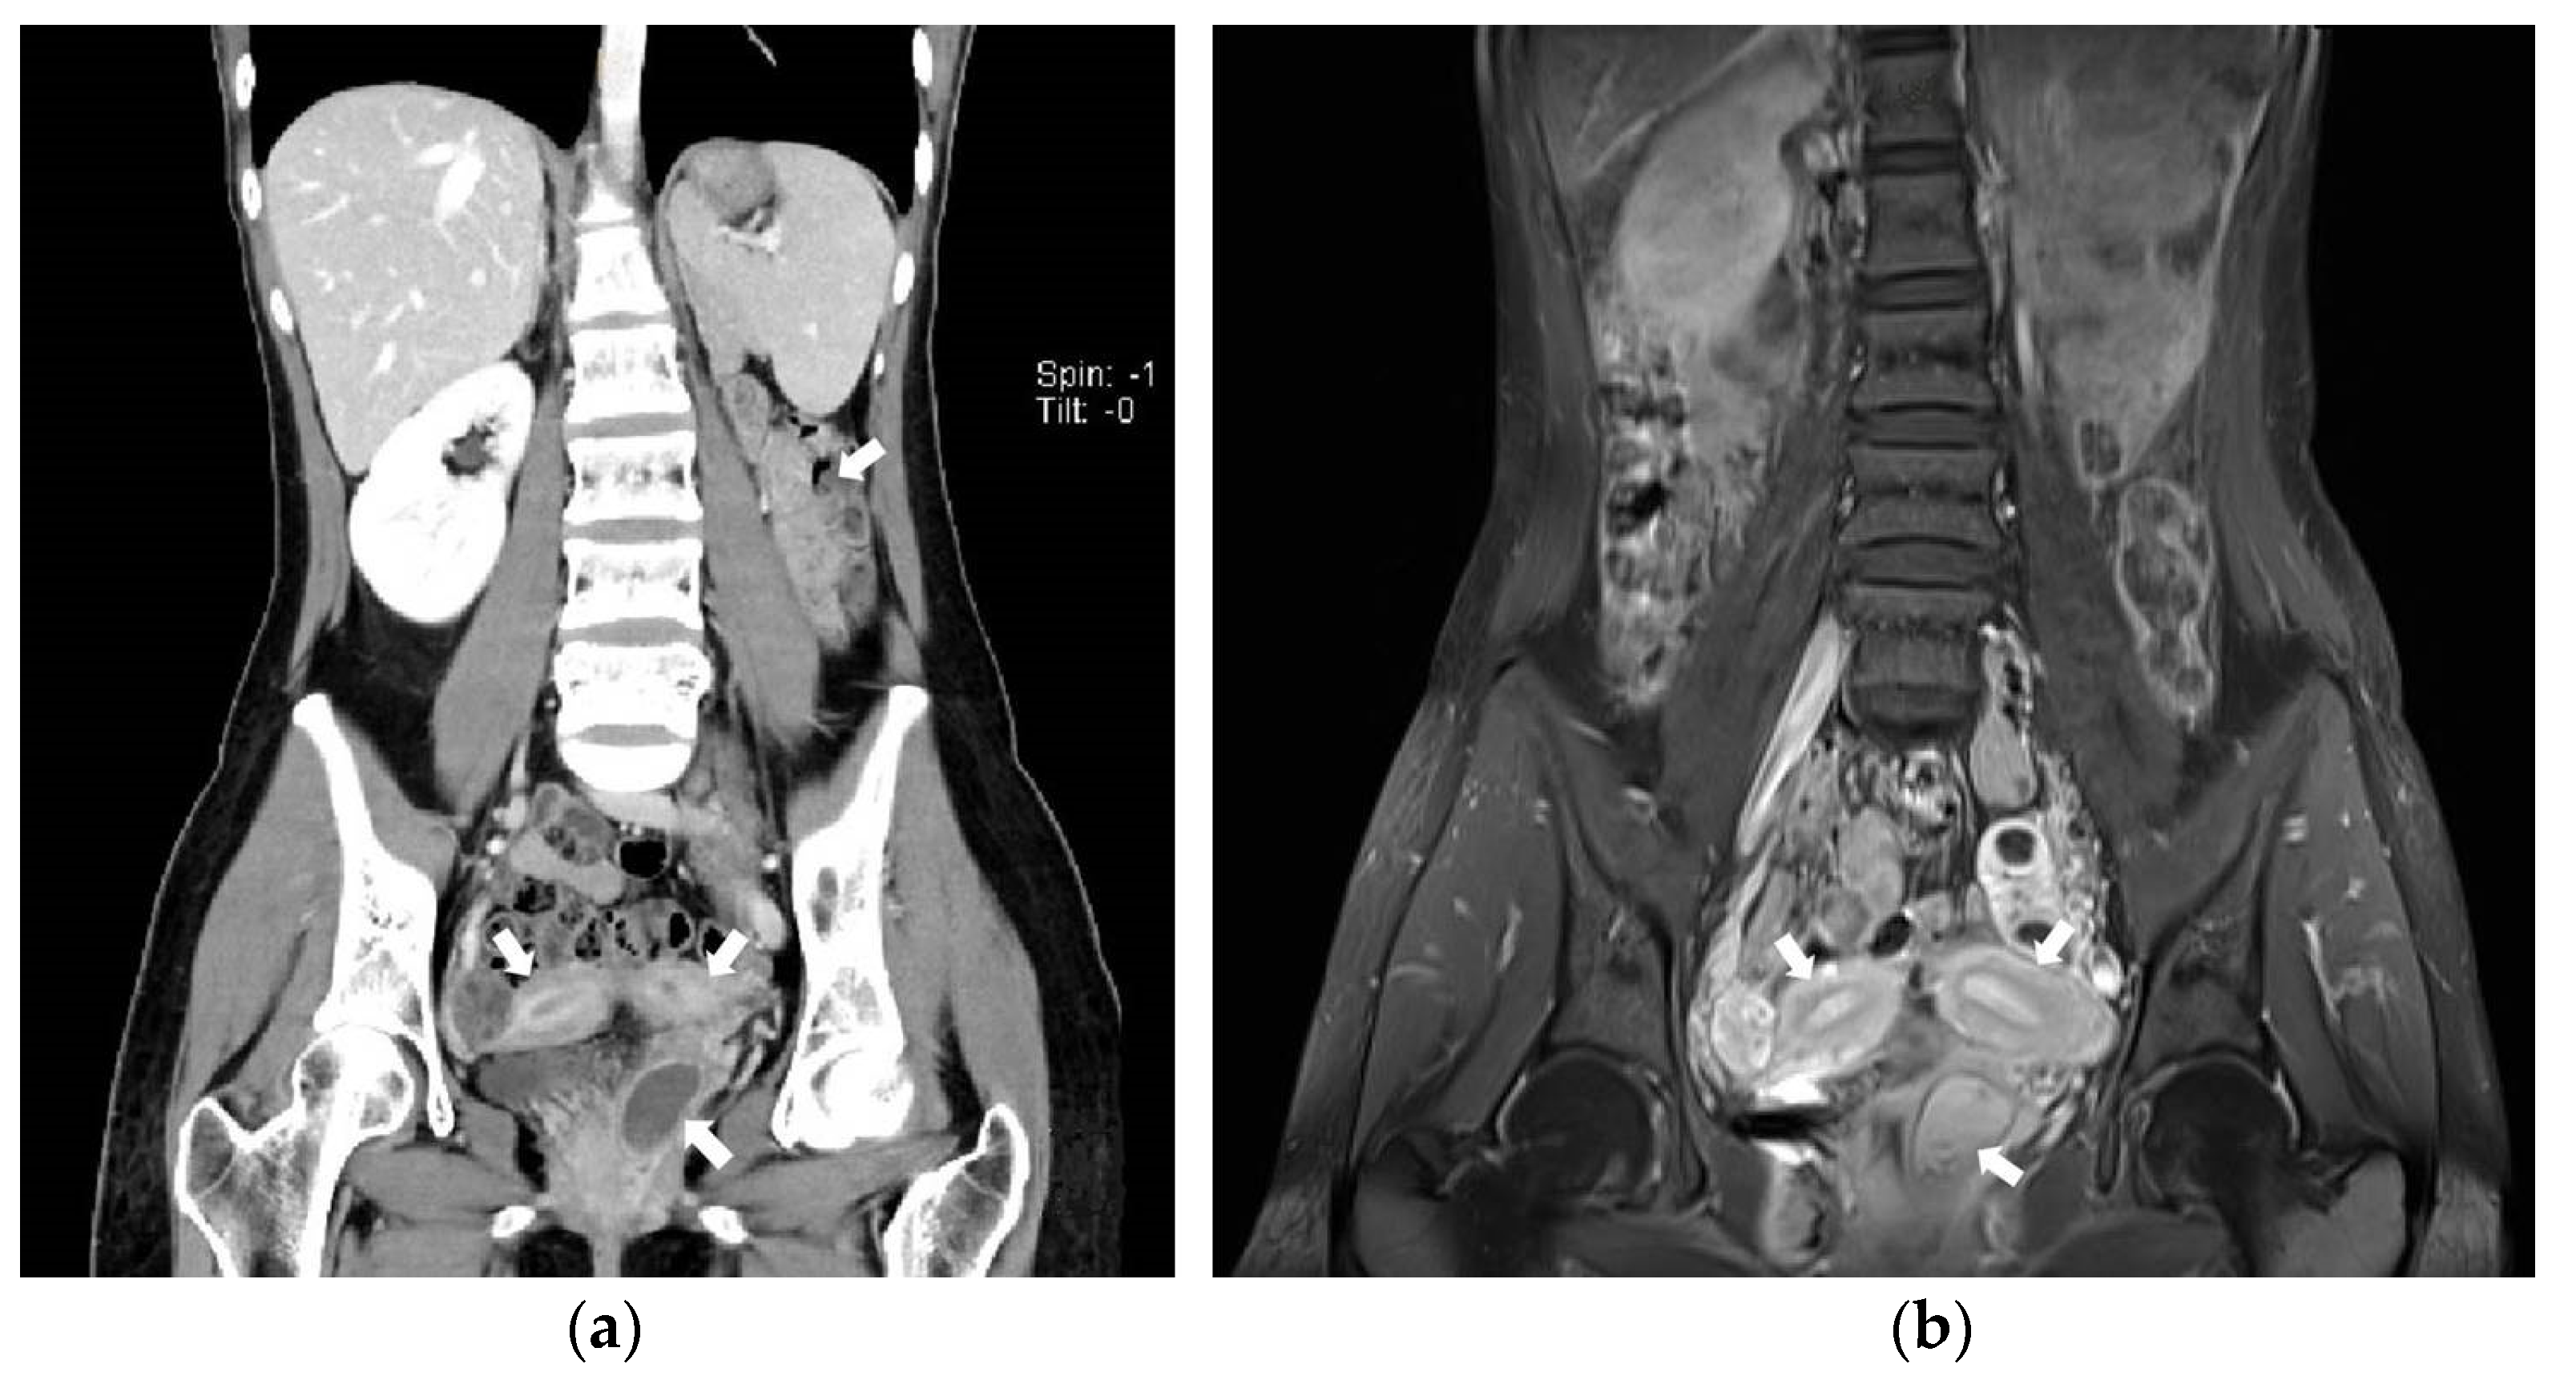

A 23-year-old unmarried woman with no history of coitus came to the Gastroenterology department presenting with acute-onset cramping pain of the left lower abdomen. The patient was referred to the Gynecology department after undergoing an abdominopelvic CT scan, during which one of our radiologists reported “uterus didelphys or bicornuate uterus with left par-ovarian or ovarian cyst” (Figure 1a).

Figure 1.

(a) Coronal view of abdominopelvic CT image suggesting Herlyn-Werner-Wunderlich syndrome. Uterine didelphys, hematocolpos of obstructed hemi-vagina, and ipsilateral renal agenesis are noted with white arrows.; (b) Coronal view of pelvic MRI T1-weighted image suggesting Herlyn-Werner-Wunderlich syndrome. Uterine didelphys and hematocolpos are noted with white arrows.

Having been informed that the patient had one kidney, we noticed the patient had HWW syndrome, so we performed a pelvic MRI (Figure 1b)

Pelvic USG and abdominopelvic CT are useful diagnostic tools. Pelvic MRI is strongly recommended as it provides thorough information on the shape of the uterus, vaginal cavity and vaginal septum [6]. In case 1, the obstructed hemi-vagina was more easily identified on MRI than CT images.